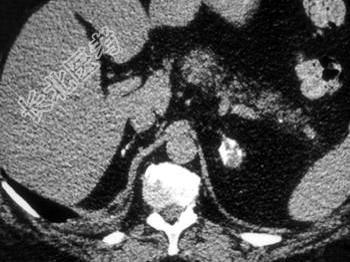

- 单项选择题根据所提供的图像,最可能的诊断是 ( )

A、结核病

B、肾上腺腺瘤

C、肾上腺癌

D、转移癌

E、嗜铬细胞瘤